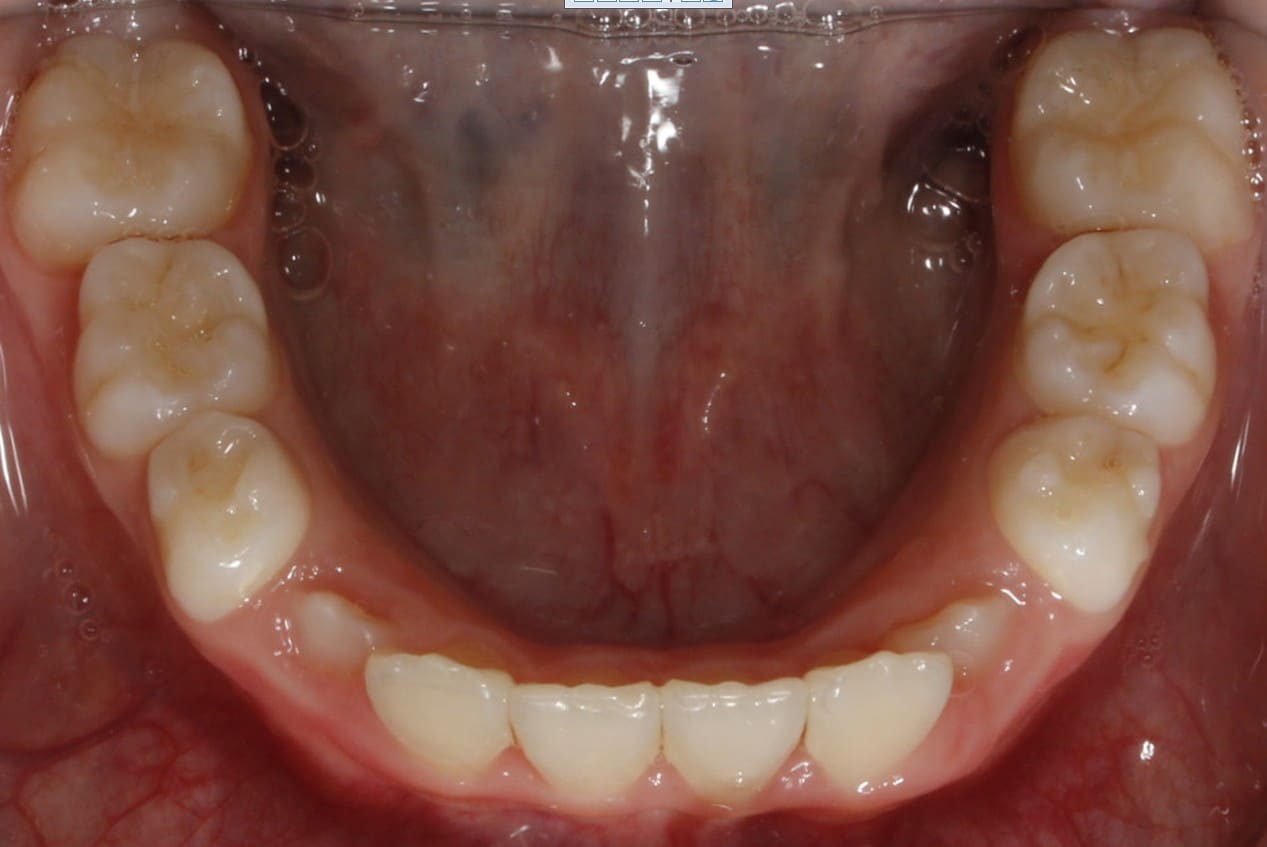

Phase I treatment with an Expander and Invisalign aligners